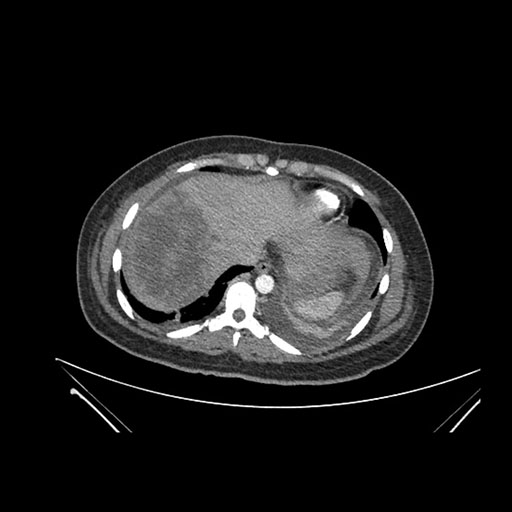

Axial Arterial

Axial Venous